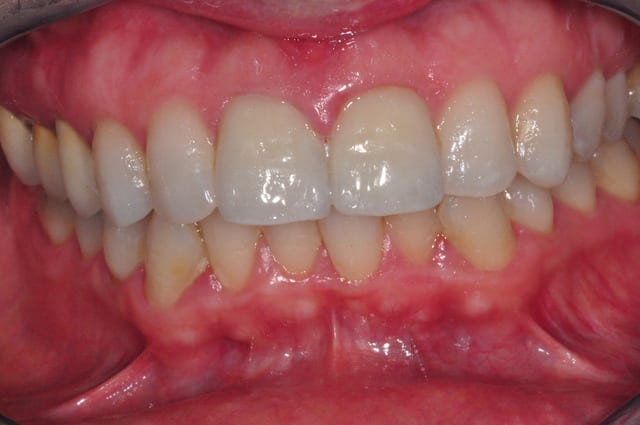

savez-vous quelle est la raison de cette porosité de surface ?

il s'agit d'emax sur 11 21 22.

non en fait ma question porte sur l'état de surface de mes emax,

la coloration est présente depuis un bon moment et je n'en connais pas l'origine

je joins une photo avant traitement